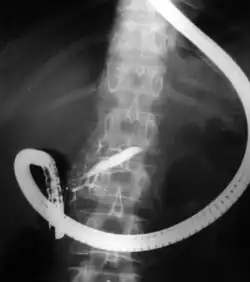

Fluoroscopic image showing dilatation of the pancreatic duct during ERCP investigation. Endoscope is visible.